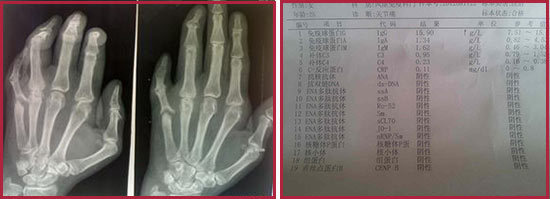

(图:类风湿性关节炎常规检查和X线检查结果)

、X光片检查:早期X线可以看到受累关节周围软组织肿胀,晚期为关节半脱位、畸形及强直。

第二、类风湿因子:对于诊断具有比较重要的参考价值。但是类风湿因子阴性不能排除本病的可能,须结合临床。

第三、C反应蛋白及血沉:C反应蛋白与病情活动指数、晨僵时间、握力、关节疼痛及肿胀程度、血沉和血红蛋白水平密切相关,病情缓解时C反应蛋白下降,反之则上升。C反应蛋白水平持续不降多提示病变的进展,病情加重则血沉加快,病情缓解时可恢复至正常,但约有5% 的类风湿关节炎患者在病情活动时血沉并不增快。

第四、血常规:类风湿性关节炎患者可伴有贫血,白细胞数大多正常,在活动期可略有增高。贫血和血小板增多症与疾病的活动相关。多数病例的红细胞沉降率在活动性病变中常增高,可为疾病活动的指标。血清铁、铁结合蛋白的水平常减低。